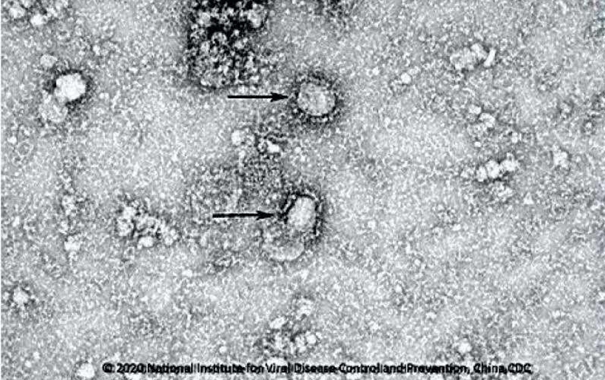

研究揭示新型冠状病毒2019-nCoV或来源于蝙蝠